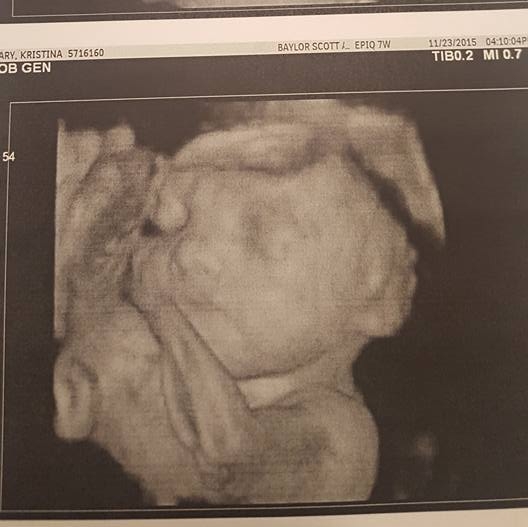

We found out just recently that our unborn daughter was diagnosed with trisomy 18.Trisomy 18 or Edward's Syndrome is not a relatively common syndrome and is fatal. This condition is caused by the presence of an extra number 18 chromosome, which leads to multiple abnormalities including severe mental retardation, digestive problems, heart failure, renal failure, respiratory failure, blindness, deafness and extreme physical limitations. Approximately 95% of fetus' with trisomy 18 are miscarried or stillborn. Most children born with this defect die within their first month. The high mortality rate is usually due to the presence of cardiac, renal malformations, and feeding problems.

When my big ultrasound day came, I thought everything would be normal as it was in the past. But after 20mins of the technician looking at the heart, followed by the doctor spending another 20 mins looking at the heart, I knew something wasn't right. I asked if everything was ok. The doctor told me there was something wrong with her heart... That her left side wasn't performing like the right side. I was heart broken. Initially, the doctor was going to send us to Houston to one of the best specialists in the country to look at Ana's heart. Within a couple days, I received the worst phone call of my life. My test results came back on my genetics blood work and we tested positive for Trisomy 18. In a matter of minutes, the outcome of mine, my fiance and my daughters life changed forever. We are heart broken! Her outcome is fatal and the inevitable will happen... She will die. We don't know how long she will live, nor is there a way to find out. But with her heart not looking good and her diagnoses, the doctor expects her time on earth to be no more than 12 hours.